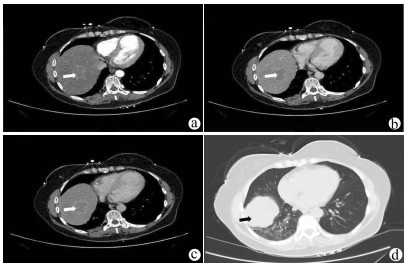

Surgical resection of liver metastases of ovarian cancer and the affected diaphragm and lung lobes via the intercostal approach: A case report